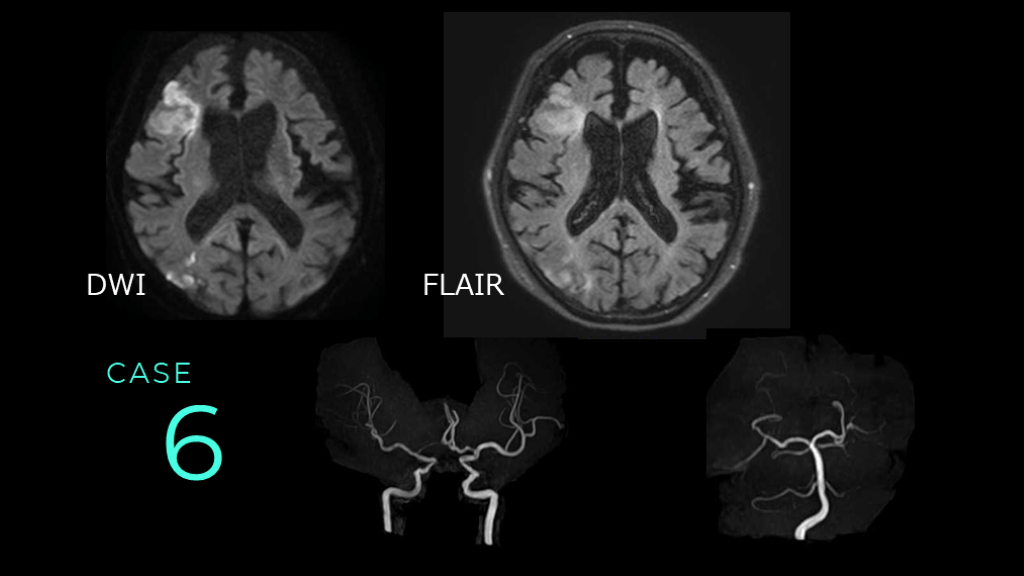

CASE 6 DWI FLAIR

CASE 6 DWIでは右前頭葉の皮質と白質に高信号病変を認める。また、側頭葉の皮質・白質にも高信号病変がある。これら病変は、FLAIRでも淡い高信号変化を認める。

CASE 6 ACAは両側左のICAからの血流が主である。 左のVAは描出なく、先天性低形成が疑われる。 これらはnormal variantsと推測される。

CASE 6 コメント:アテローム血栓性脳梗塞症例。皮質と白質を含む病変であること、前頭葉と側頭葉にあること、DWIとFLAIRでHIGHであることを述べる。